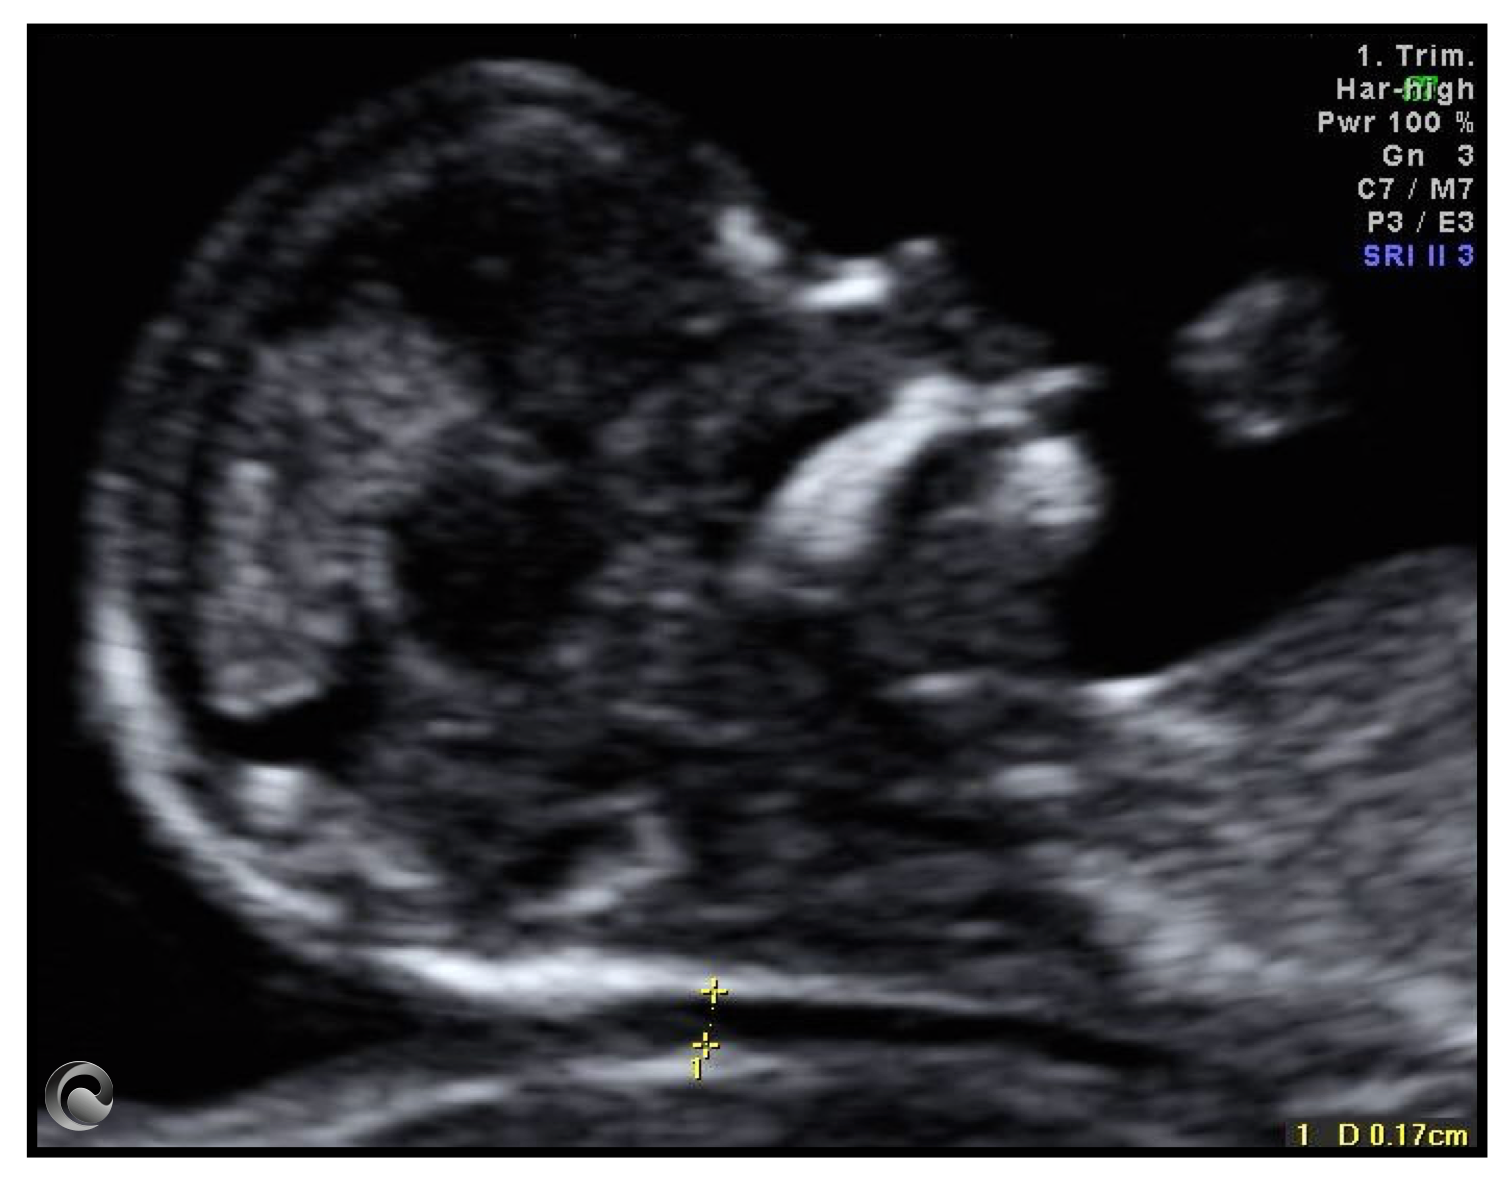

Plano mediosagital estricto de la cara fetal entre las 11-13 semanas en el que mide la translucencia nucal y se evalúa la presencia del hueso nasal